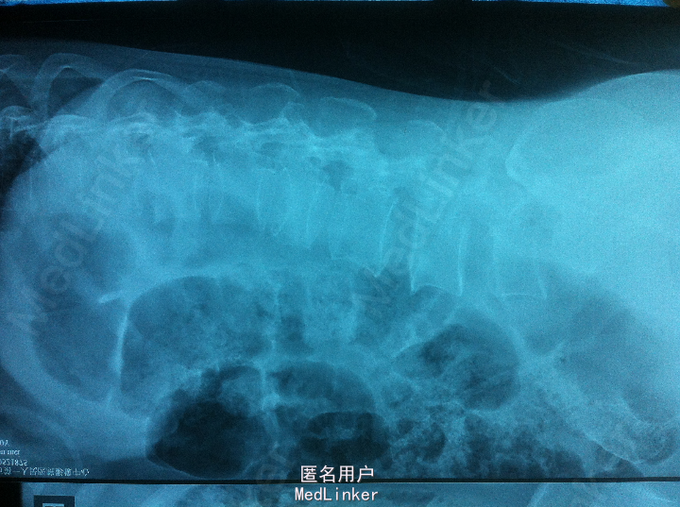

高处摔伤腰部疼痛、活动受限1入院。 中年女性,既往健康; 患者1天前从3米高处摔伤,臀部着地,及感腰部疼痛、活动受限,双下肢无放射性疼痛、麻木,双下肢活动可。

PE:腰部轻度后凸,叩痛,双下肢感觉无减退,双下肢肌力4-5级,巴氏征 阴性。 X-ray:腰2椎体骨折 CT:腰2椎体骨折,椎体后缘不连续 MR:腰2椎体骨折,腰2-3椎体水平硬膜外血肿

诊断:腰椎骨折 腰椎硬膜外血肿 处理:腰椎后路撑开复位内固定